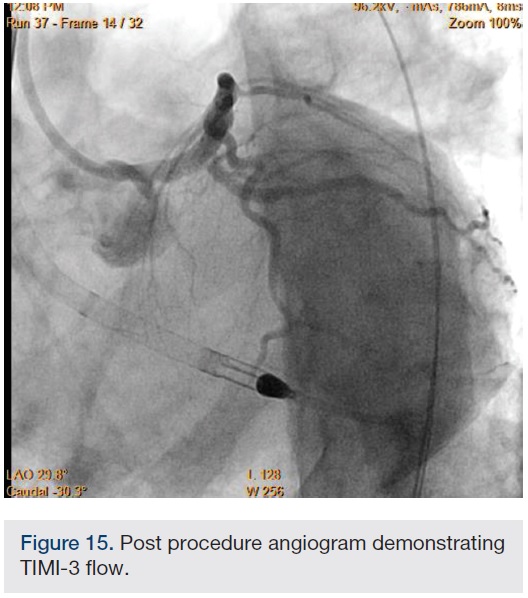

Following successful completion of the peripheral phase, it was felt that a 4-week period was necessary for the iliac stent to heal somewhat (especially since we planned to place a 14 French Cook sheath through it). We then moved on to the coronary phase of this procedure. Bilateral groins and the right wrist were prepared and draped in the usual sterile fashion. Using micropuncture technique with fluoroscopic verification of needle entry into the left CFA at the upper quadrant of the femoral head, a 6 French sheath was placed in the left CFA. The existing left femoral arterial sheath was removed, and the arteriotomy was pre-closed with a single Perclose device (Abbott Vascular). The arteriotomy was then serially dilated with 10, 12 and 14 French dilators, and a 14 French, 30 cm Cook sheath was placed successfully in the left common femoral artery. Following therapeutic anticoagulation with intravenous heparin, a regular J-wire and a 6 French pigtail catheter were used to cross the aortic valve, and the catheter was used to exchange the J wire for the 0.018-inch Platinum Plus wire (Boston Scientific). The Impella CP (3.5) percutaneous left ventricular assist device (LVAD) (Abiomed) was inserted into the left ventricle over the Platinum Plus wire (Figure 8). The Impella was then activated and good flows were verified. Right radial artery access was obtained and a PB 3.0 7.5 French sheathless guide system (Asahi Intecc) was used to engage the left main coronary artery. The LAD was wired uneventfully using a Runthrough wire (Terumo) via a 1.25 x 6 mm over-the-wire (OTW) Sprinter balloon (Medtronic). This was then exchanged for a Viper wire (CSI). Orbital atherectomy of the proximal LAD lesion was performed with excellent results (80,000 rpm x 4 passes, 120,000 rpm x 2 passes) (Figure 9). The LAD wire was then exchanged for a Runthrough wire and the left circumflex (LCX) was wired with a BMW wire. Following plaque modification with orbital atherectomy, predilation of LAD was performed with 3.0 x 20 mm Chocolate Balloon (QT Vascular Ltd) (15 atmospheres x 60 seconds and 15 atmospheres x 30 seconds) (Figure 10) with an excellent result and no dissection (Figure 11). A 3.5 x 38 mm Promus stent (Boston Scientific) (14 atmospheres x 30 seconds) was placed from the left main into the proximal LAD lesion ensuring adequate coverage. The jailed LCX wire was recovered and re-placed in the LCX through the struts of the newly placed LM-LAD stent (Figure 12). Predilation of the LCX ostium was performed with a 2.5 x 8 mm Glider balloon (QT Vascular Ltd) (14 atmospheres x 25 seconds). The mid LAD was stented (ensuring overlap with proximal stent) with 3.0 x 16 mm Promus stent (16 atmospheres x 25 seconds). A final kissing balloon inflation of the LAD/LCX with an NC Sprinter 2.5 x15 mm balloon (Medtronic) into the LCX and a NC Sprinter 3.5 x12 mm balloon into the LAD was performed, with up to 16 atmospheres x 20 seconds on both (Figure 13). Final IVUS of the LM and LAD stent revealed excellent results and the LCX ostium looked excellent as well (Figures 14-16).